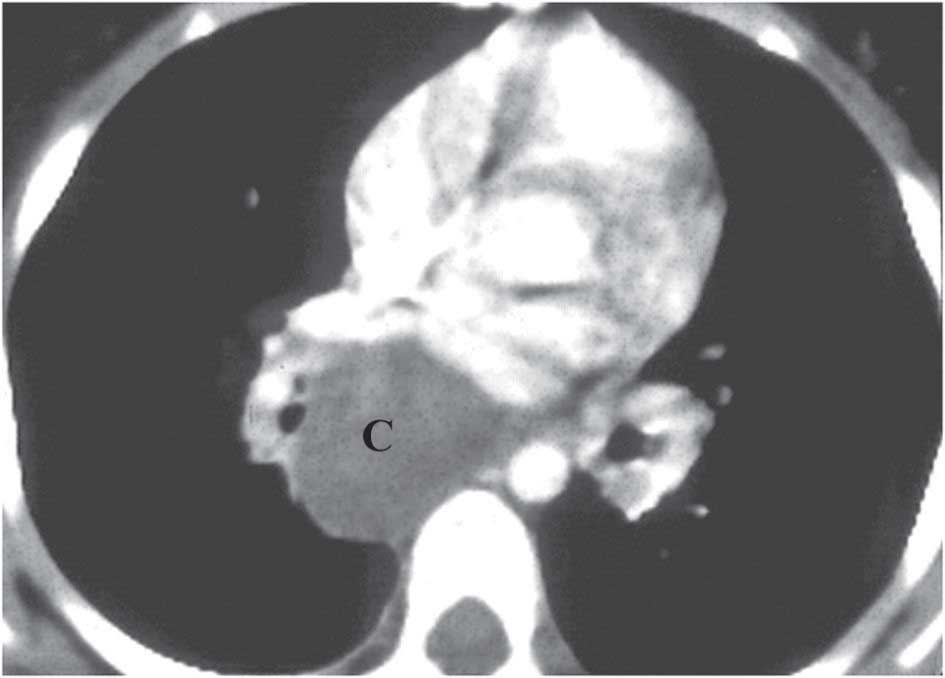

5- الكيسات القصبية:

أكثر ما تتوضع الكيسات القصبية في المنصف الخلفي بمحاذاة المهماز الرغامي، وقلما تتوضع في السرة الرئوية أو في المتن الرئوي، وتبقى الكيسات المنصفية لاعرضية وتكشف اتفاقاً في الكهول، ولكنها قد تضغط الطرق الهوائية في الأطفال. يوضع التشخيص بالتصوير المقطعي المحوري. تعالج الكيسات المنصفية والسرية باستئصال الكيسة فقط، أما المتوضعة في المتن الرئوي فتعالج باستئصال الشدفة أو الفص المصاب (الشكل 2).

![]() | ![]() |

الشكل (2 - أ) يظهر ترسيمياً توضع الكيسات القصبية الخلقية في المنصف الخلفي أو في السرة الرئوية أو في المتن الرئوي | الشكل (2 - ب) يُظهر التصوير الطبقي المحوري للصدر الكيسة القصبية المنصفية خلف القلب أسفل التفرغ الرغامي |